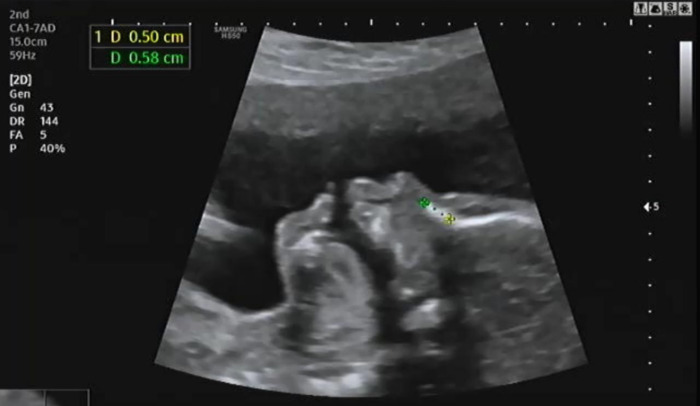

태아의 옆모습을 보며 콧대를 확인한다. 코뼈 길이를 측정하는데 엄마를 닮았는지 코뼈 길이가 짧아 의사가 두 번이나 측정해서 겨우 0.58cm임을 확인했다. 코뼈 길이를 측정할 때 무안해서 남편이랑 눈을 마주치자마자 슬며시 웃었다.